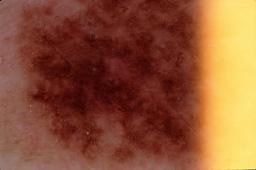

{

"age_approx": 70,

"anatom_site_general": "head/neck",

"concomitant_biopsy": true,

"dermoscopic_type": "contact non-polarized",

"diagnosis_1": "Benign",

"diagnosis_2": "Benign epidermal proliferations",

"diagnosis_3": "Solar lentigo",

"diagnosis_confirm_type": "histopathology",

"image_type": "dermoscopic",

"lesion_id": "IL_0613739",

"melanocytic": false,

"patient_id": "IP_0690933",

"sex": "male"